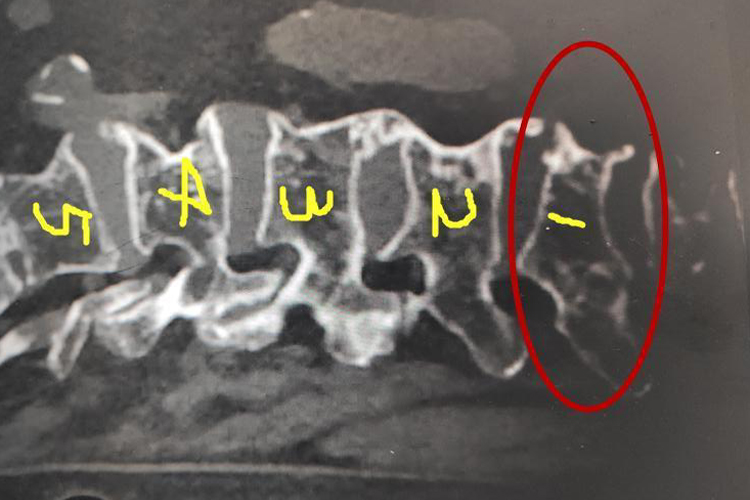

腰1椎体楔形变可由腰椎骨折、骨质疏松症或腰椎骨肿瘤引起椎体发生压缩性骨折,椎体前方高度塌陷,椎体呈楔形或梯形的形态。

在腰1椎体发生骨折时,通过X线片可以观察到腰1椎体楔形变,伤处局部会发生腰痛,同时腰部会有明显压痛,伸屈下肢感腰痛。

当腰1椎体发生骨肿瘤时,X线片上可呈膨胀性溶骨性间隔性病变,肿瘤可使腰椎骨结构破坏,导致腰1椎体楔形变。